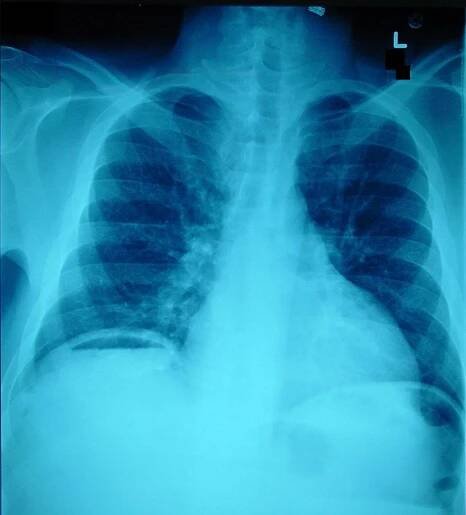

Spontaneous Intestinal Perforation | Applied Radiology

File:Pneumoperitoneum X-ray.jpg - Wikipedia